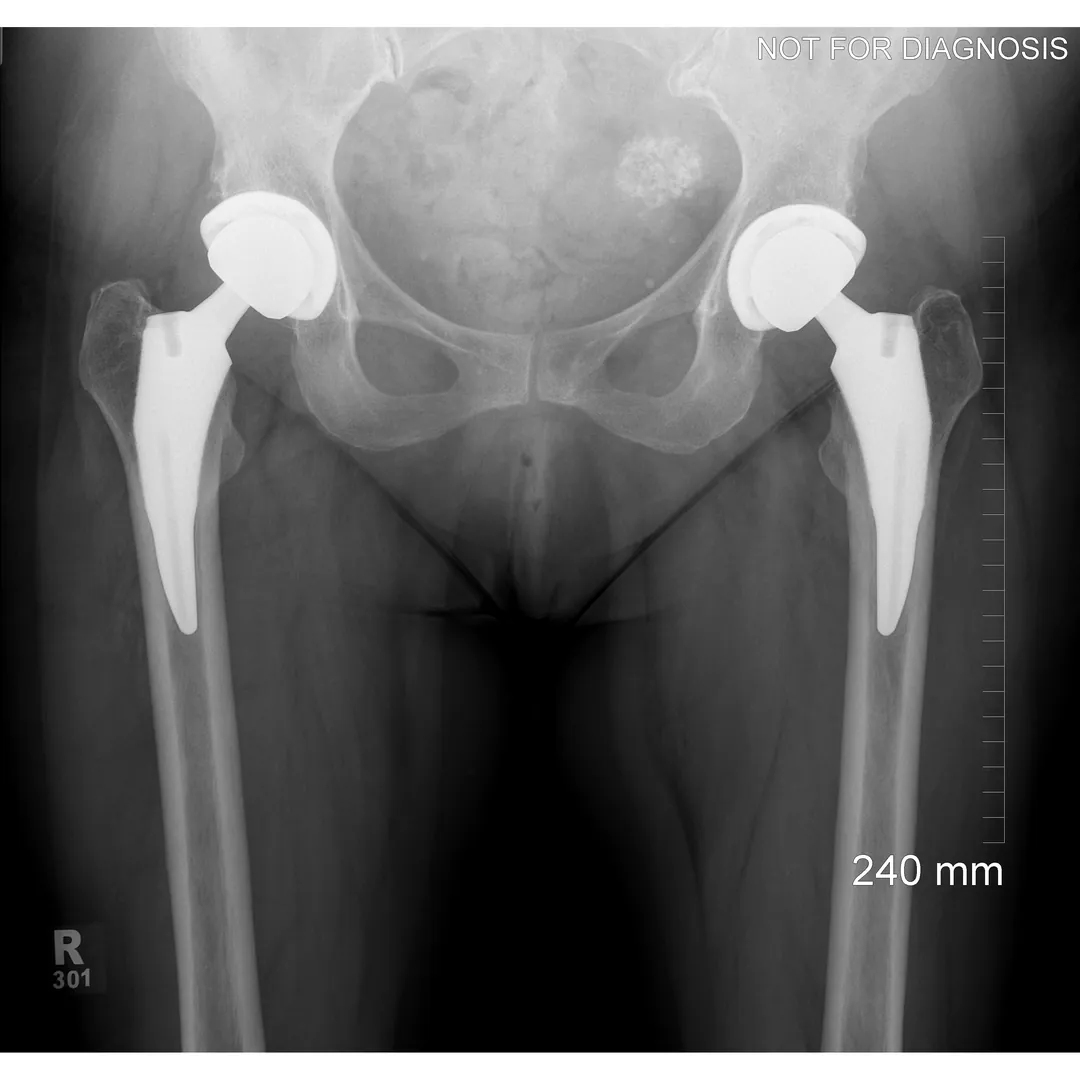

A total hip replacement (also called total hip arthroplasty) is a surgical procedure in which a damaged or worn hip joint is replaced with artificial components. The hip is a ball-and-socket joint, meaning the ball at the top of the thigh bone sits in a socket on the pelvis. During surgery, the damaged ball (femoral head) is replaced with a metal or ceramic ball attached to a stem, and the damaged socket is replaced with a metal cup lined with plastic, ceramic, or metal.

- The surgeon removes the damaged bone and cartilage and inserts the artificial joint